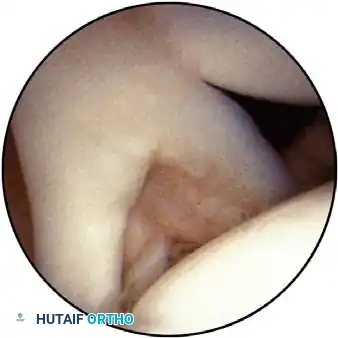

Routine diagnostic arthroscopy is performed using a 4-mm, 30-degree oblique arthroscope. This angle allows for comprehensive visualization of the entire joint through rotation of the lens and manipulation of the arm. In complex instability cases, switching to a 70-degree arthroscope dramatically improves visualization of the anterior glenoid neck and the inferior glenohumeral ligament, which is critical during arthroscopic capsulorrhaphy.

Once diagnostic evaluation is complete and hemostasis is secured, the therapeutic phase commences. Whether performing a SLAP repair, a Bankart stabilization, or a rotator cuff repair, the principles of tissue mobilization, anatomical footprint restoration, and secure biomechanical fixation remain paramount.